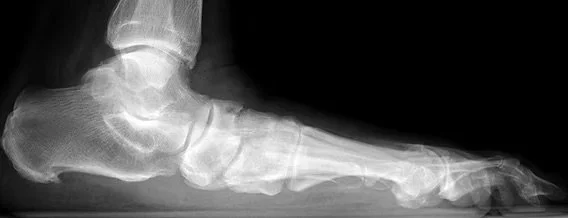

Flatfoot, also known as pes planus, is a condition in which the arch of the foot collapses or fails to maintain its normal shape during standing and walking. While some people are born with flexible flatfeet that remain painless, others develop progressive flatfoot deformity in adulthood, often associated with pain, instability, and functional limitations.

The arch of the foot is maintained by a combination of bones, ligaments, and tendons, most notably the posterior tibial tendon. Flatfoot develops when these supporting structures weaken or fail, allowing the arch to collapse and the heel to drift outward.

Adult flatfoot is often progressive, meaning the deformity and symptoms worsen over time if left untreated. As alignment changes, abnormal forces are placed on the foot and ankle joints, which can lead to pain, fatigue, instability, and eventual arthritis. Flatfoot may be flexible in early stages but can become stiff and rigid as degeneration progresses.

Diagnosis of flatfoot begins with a comprehensive clinical examination, focusing on foot alignment, arch height, heel position, and overall gait mechanics. Evaluation includes assessment of hindfoot flexibility, tendon strength, and areas of tenderness.

Weight-bearing X-rays are typically used to confirm the diagnosis and assess the severity of deformity, joint alignment, and the presence of arthritis. Advanced imaging such as MRI may be obtained in select cases to evaluate tendon integrity or associated soft-tissue pathology.